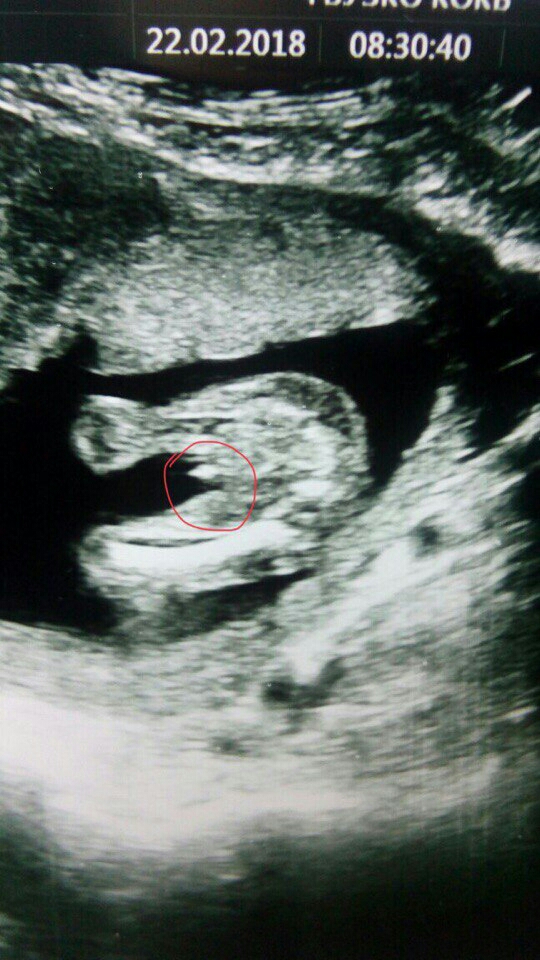

@valerialimpieva та никуда он уже не денется,вон как выглядывает ))))я третьего такого перчика ношу))) второго как носила ,мне яички крупным планом показывали на УЗИ ,чтобы в парне не сомневалась))

@oksankaartem2011 дааа, надеюсь так и останется) 97 % обещают))